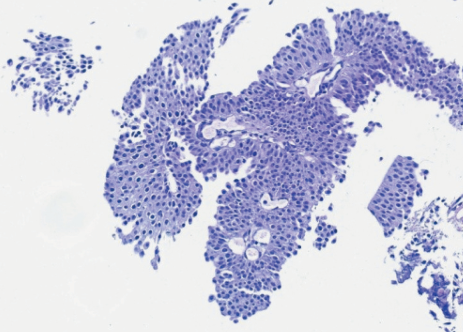

2. Рис. 2. Микрофото. Опухоль папиллярного строения с увеличением количества слоев, ядерной гиперхромией и клеточным полиморфизмом. Неинвазивная папиллярная уротелиальная карцинома Low Grade. Окраска гематоксилином и эозином, ×20. Примечание: рисунок выполнен авторами

Клиническое наблюдение. В урологическом стационаре ЧУЗ ЦКБ «РЖД-Медицина» Nd:YAG-лазерная абляция немышечно-инвазивного рака мочевого пузыря труднодоступной локализации проведена пациенту, 67 лет, с образованием по передней стенке МП. При гистологическом исследовании биоптата образования мочевого пузыря верифицирован рак мочевого пузыря. Поверхностный характер роста опухоли подтвержден по результатам магнитно-резонансной томографии, проведенной до операции. Для лечения применяли Nd:YAG-лазер с длиной волны 1 064 нм, мощностью 40 Вт и плотностью энергии 100 Дж/см2 . Лазерное излучение подавалось через световод с боковым выходом (Side Fire). После операции в МП установлен двухходовый катетер на 12 ч. Интра- и послеоперационных осложнений не было. Эндоскопический мониторинг эффективности хирургического этапа лечения проводился на базе ЧУЗ ЦКБ «РЖД-Медицина» с кратностью 3, 6 и 12 мес с момента операции, при этом признаков рецидива не обнаружено.